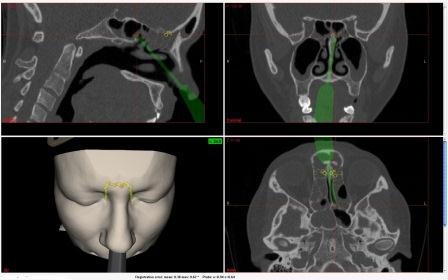

Das chirurgische Cockpit (auch OP-Saal der III. Generation) verfügt jetzt über ein zusätzliches elektromagnetisches Messverfahren, mit dem die aktuelle Position der Instrumentenspitze erkannt werden kann.

Bislang wurde hier ausschließlich auf die bewährten und hochgenauen optischen Messverfahren zurückgegriffen. Mit Hilfe der zusätzlichen elektromagnetischen Messung kann bei Abdeckung der sogenannten Sichtachse zwischen optischer Messkamera und Instrument die Funktion der Navigation (tool tracking) bei ausreichender Genauigkeit weiter gewährleistet bleiben. Dadurch steigt die Verlässlichkeit der Navigationsfunktion. An der ACQUA Klinik fand jetzt in Zusammenarbeit mit dem IRDC Leipzig, der TU München und der Fa. KARL STORZ der erstmalige Einsatz dieser Verfahren statt. „Insbesondere für flexible Instrumente ergeben sich durch die alternative Positionsbestimmung neuartige Möglichkeiten der Navigation." erläutert Iris Gollnick, Centre Managerin des IRDC, einem Unternehmen für Entwicklung von Medizintechnik mit Sitz in Leipzig und Partner von namenhaften deutschen Herstellern der Branche.